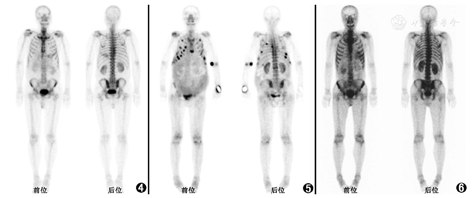

本例全身骨显像除骨折的表现之外,以多发外周关节、臀部及双下肢对称性皮下受累为主要表现。首先来看骨外软组织99Tcm-MDP摄取。除去药物因素和尿液污染等技术因素,骨外摄取的机制分为4类[1]:(1)转移性钙化(metastatic calcification),指高钙血症状态下钙离子在组织沉积,引起99Tcm-MDP浓聚,常见病因包括原发或继发性甲状旁腺功能亢进(图2)、肿瘤相关的骨破坏等;(2)营养不良性钙化(dystrophic calcification),指组织损伤(如外伤、缺血、细胞坏死)造成的组织内钙离子沉积,患者血钙浓度通常正常,常见病因为脑梗死(图3)、心肌梗死、镰状细胞贫血或淋巴瘤等导致的脾梗死、过度运动引起的骨骼肌损伤、术后瘢痕、皮肌炎等;(3)代谢性钙化(metabolic calcification),指由于某些代谢性因素,病变部位有局灶性的成骨活性,表现为摄取99Tcm-MDP,常见病因为骨肉瘤转移灶、外伤或炎性反应诱发的骨化性肌炎、黏液腺癌、淀粉样变(图4);(4)被隔离(sequestration),指组织对99Tcm-MDP的洗脱速度较慢,导致局部99Tcm-MDP浓度高于本底,常见病因有胸腹腔积液(图5)、静脉或淋巴梗阻、肠道淋巴管扩张、蛋白丢失性肠病。本例患者外伤及手术后出现骨外摄取,需考虑软组织损伤引起的营养不良性钙化或创伤后诱发的骨化性肌炎,但患者双下肢骨外摄取分布对称,外伤侧未见明显加重,不符合软组织损伤、骨化性肌炎导致的骨外摄取特点。结合患者高龄、多发骨折的病史,需考虑肿瘤相关骨外摄取、病理性骨折、或严重骨质疏松致骨折等。

多发性骨髓瘤骨显像也可表现出骨外摄取。当多发性骨髓瘤出现高钙血症时,由高钙血症引起的99Tcm-MDP骨外摄取可见于多个器官,肌肉等软组织也可发生广泛的99Tcm-MDP摄取;此外,多发性骨髓瘤出现软组织99Tcm-MDP摄取,还需考虑合并淀粉样变的可能性[3]。淀粉样变主要分为原发性淀粉样变(由浆细胞疾病如多发性骨髓瘤导致,蛋白质沉积物为免疫球蛋白轻链)、继发性淀粉样变(多由慢性炎性疾病导致,蛋白质沉积物为血清淀粉样蛋白A)以及一些其他类型的淀粉样变[如转甲状腺素蛋白相关性淀粉样变(transthyretin-related amyloidosis, ATTR)][4]。淀粉样物质由纤维样蛋白质及非纤维样糖蛋白(P物质)构成,在各淀粉样变分型中P物质均为固定组成物,并通过钙离子依赖途径与纤维样蛋白质结合,这可能为淀粉样物质摄取99Tcm-MDP的原因[4]。

多发性骨髓瘤的淀粉样变多见于心脏、肾、消化道、肝、皮肤、肌肉、周围神经等(图6),少部分患者可发生淀粉样变关节病[7]。在一项系统性回顾研究中,共纳入101例诊断为多发性骨髓瘤相关淀粉样变关节病的患者(59例经关节滑膜液病理诊断),其中62.4%的患者在诊断多发性骨髓瘤前已有关节炎表现,大部分患者表现为大于4个关节的受累,易受累关节为肩关节、膝关节、手小关节[8]。有文献报道1例多发性骨髓瘤患者的全身骨显像表现为双肩关节、髋关节、膝关节、踝关节99Tcm-MDP高摄取,膝关节囊穿刺病理证实为淀粉样物质沉积,提示多发性骨髓瘤相关淀粉样变关节病患者的99Tcm-MDP全身骨显像可表现为多发外周关节受累[9],与本例表现相似。